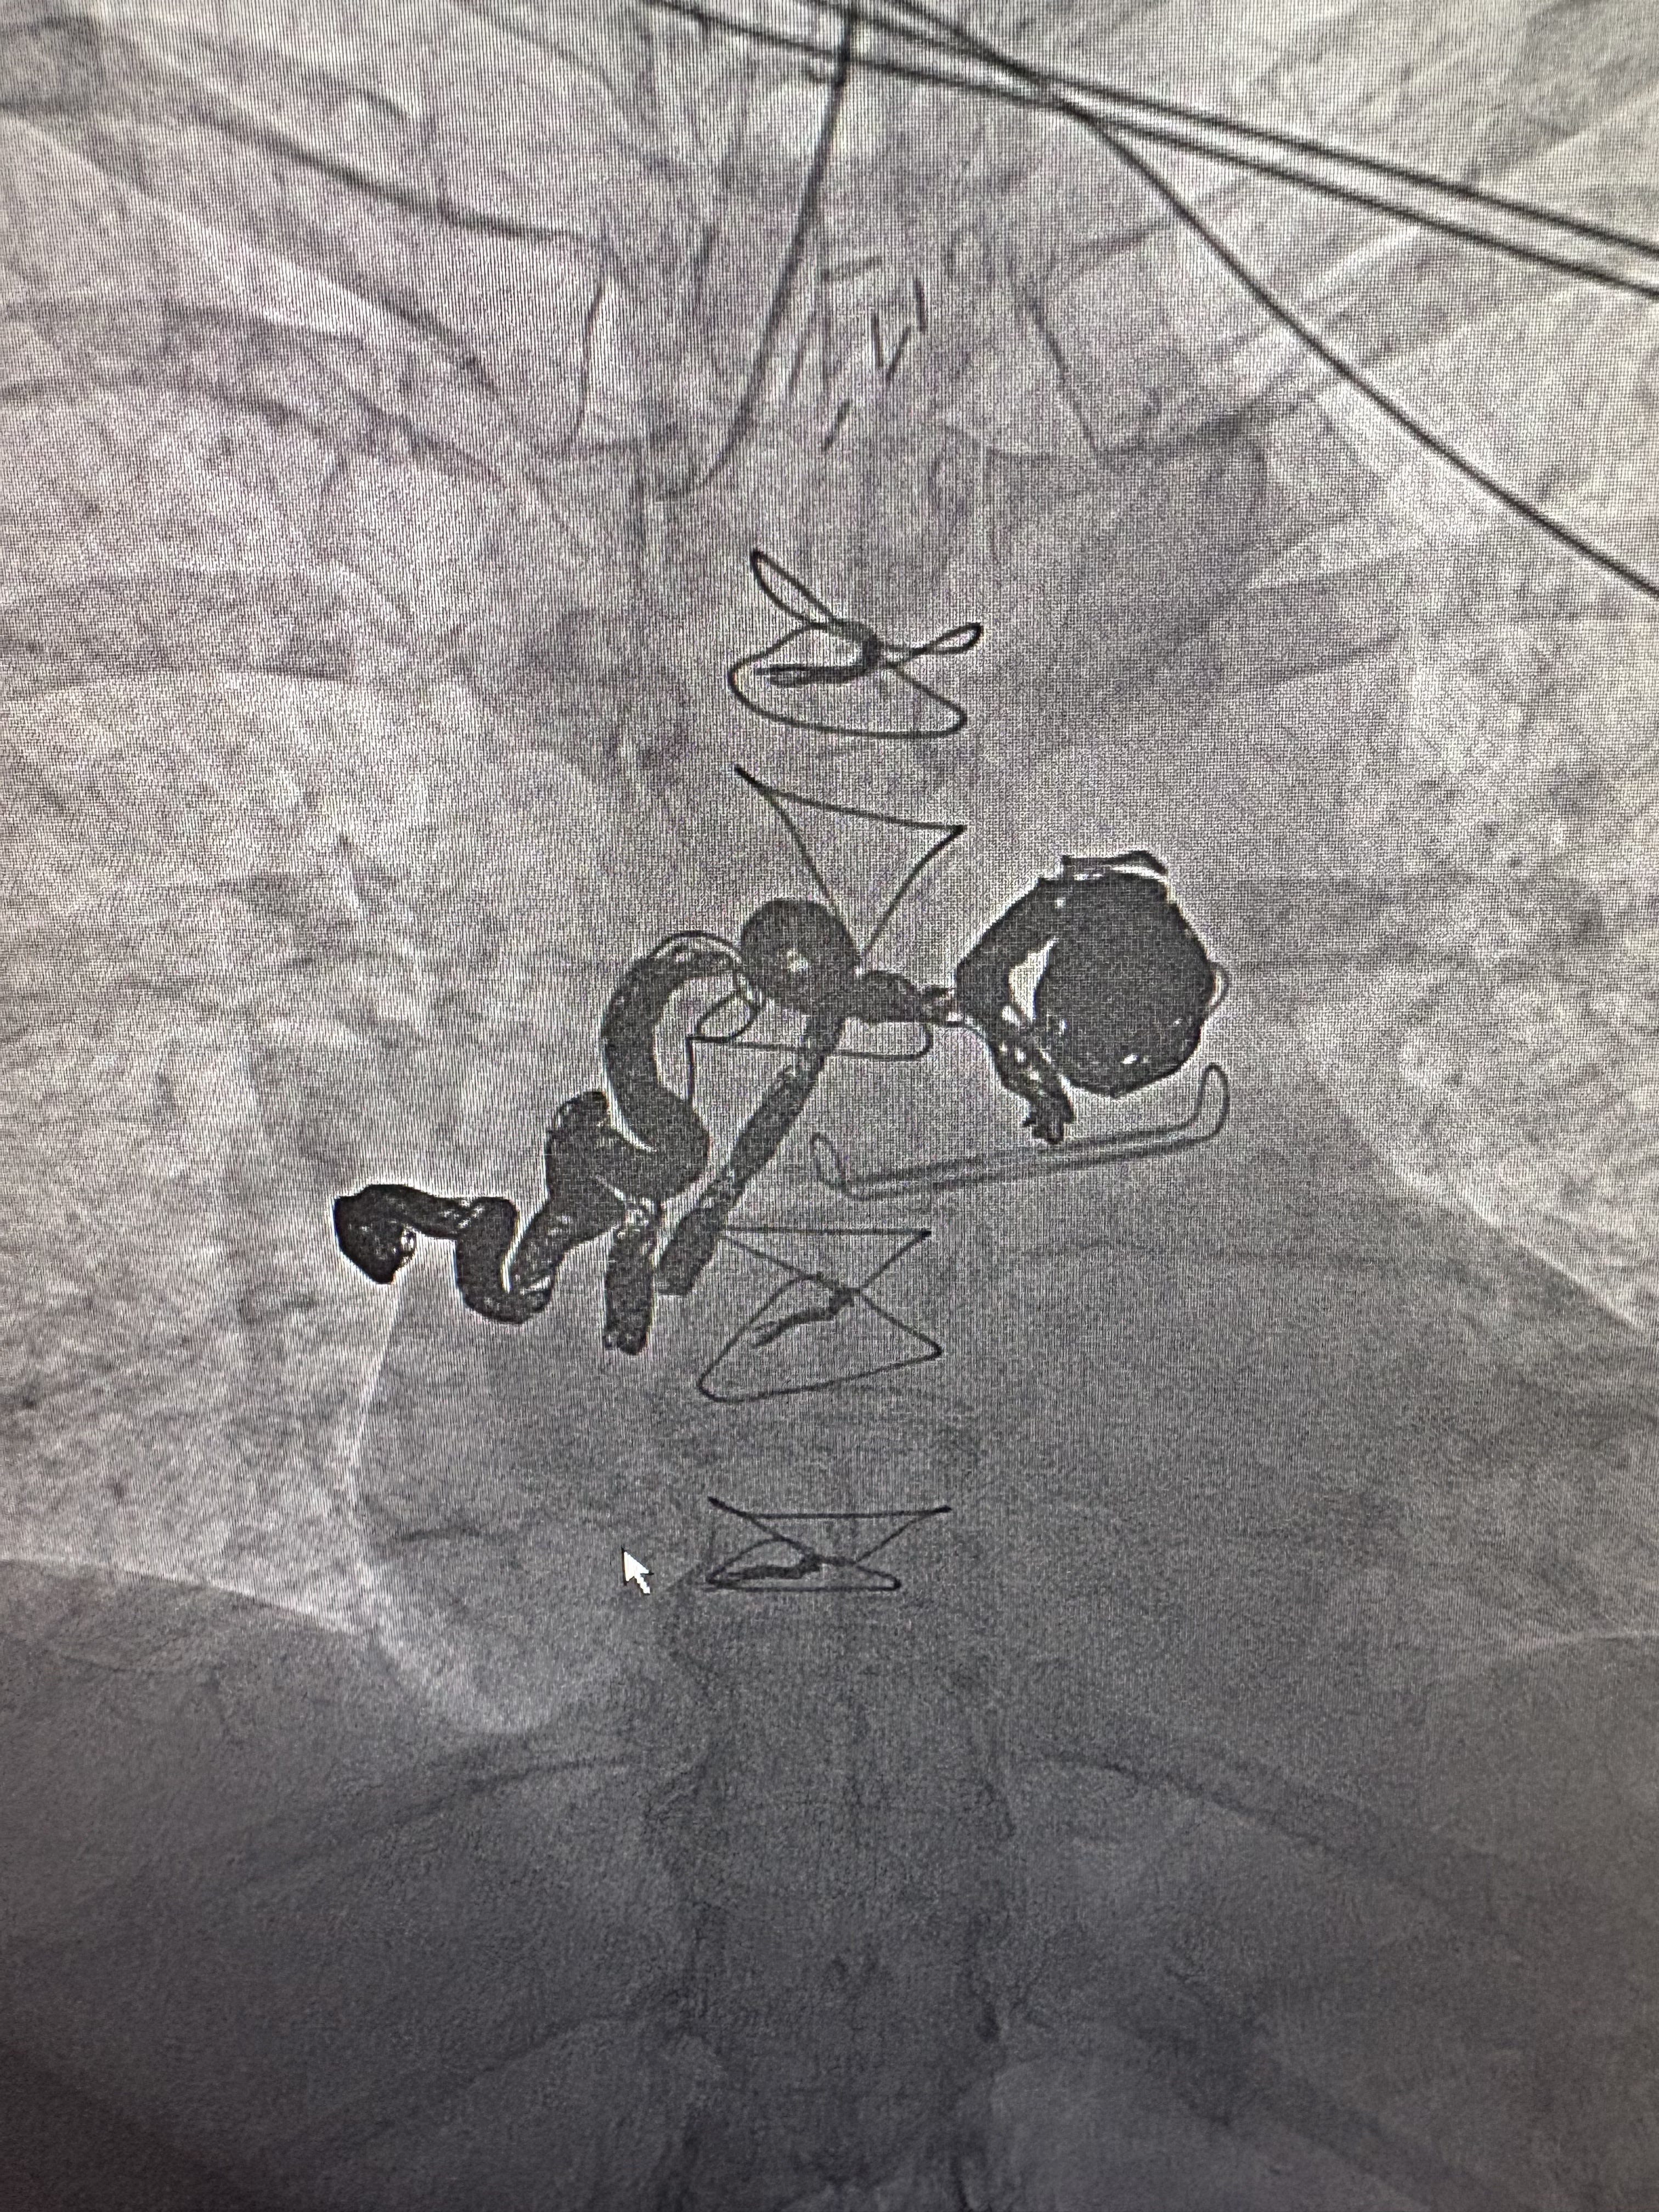

Now for the potentially boring part. Below are before and after images of my bronchial artery aneurysm and bronchial artery aneurysm to pulmonary artery fistula. As I probably mentioned on here before, each is rare, but to have them both together is “exceedingly rare.” Here’s the not boring, praise-the-Lord part: Prior to the procedure, the interventional radiologist planned to embolize the fistula as deeply as possible then see how I did and do the larger aneurysm later. But he was very happy he was able to fill nearly the whole squiggly, aneurysmal artery plus the bigger bulging artery. I now have 23 platinum coils in there. When I texted my oldest that information, he texted back, “Platinum is $2,000/oz now. Looks like me and Cam (sister) will be taking you to the pawn shop pretty soon.” So funny.